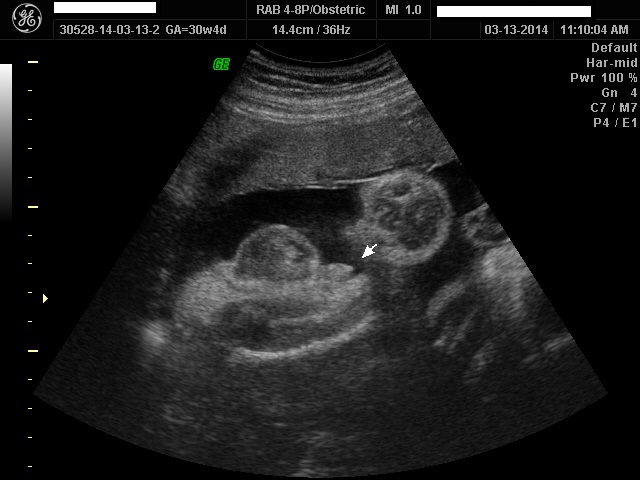

OK so this might be a realllly ridiculous question but we had our elective 3D ultrasound of our little man on Thursday. I didn't really think to much about this while we were there because I was so focused on his cute face and being over joyed that he was in fact 100% all boy. Now that I am home and looking at his pictures .. are his nuts too big? Like should I be concerned? DH is patting himself on the back but I am a little concerned .. I know when little boys are born their sacs are very large and swollen ... is that what I am seeing here? Or does my son have abnormally large balls?! So sorry if this is a really stupid question but this is my first boy and vagina's are just so much easier.

Attachment 17599

Totally normal, as others have said! That pic looks quite average to me, too. What gestation is that ultrasound?